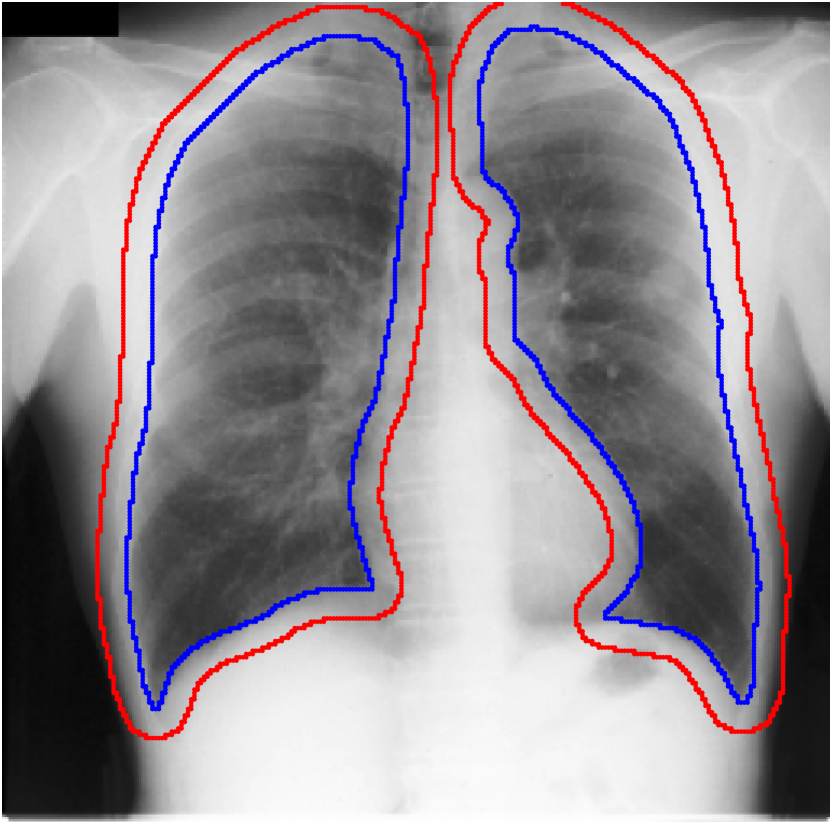

Table 1 shows the segmentation results of different methods with synthetic noisy label settings on JSRT , ISIC 2017 and Brats 2020 dataset. Note that QAM cannot be applied to Brats 2020 dataset because their network is designed for 2D only. We compare DICE score (DSC) on testing sets (against the clean labels). For each setting, we train 5 different models, and report the mean DSC and standard deviation. In and , where biases show up in noisy labels, the proposed method outperforms the baselines by a big leap in total case. The compared methods, however, only work when little bias is included, like . is equivalent to setting in our Markov model, resulting in . We also test the proposed method on real-world label noise, results shows in Table 2. Figure 5 shows examples of label correction results. We provide more qualitative results in the Appendix A.4.

For each of these three datasets, we use three noise settings, denoted by , and . and are two settings synthesized by our Markov process with (expansion) and (shrinkage), respectively. Figure 4 shows examples of our synthesized label noise. We also include the mix of random dilation and erosion noise used by previous work (Zhu et al., 2019; Zhang et al., 2020b; a). This is achieved by randomly dilate or erode a mask with a number of pixels. Note that our Markov label noise can theoretically include this type of noise by setting . Detailed parameters for these settings are provided in the Appendix.